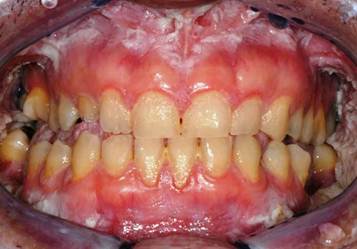

An 38 year-old Italian man came to the Department of Oral Hygiene and Periodontology at Calabrodental clinic in April 2011 for the evaluation of white bilateral corrugated plaques developed on the buccal mucosa and on the gingiva, these plaques were been present since he was 13 years-old. (Fig.1)

a patient showing white bilateral corrugated plaques developed on the buccal mucosa and on the gingiva.

These plaques were always asymptomatic, however, from 2 months, the patient complained of burning symptoms that persisted throughout the day. So, he came at the clinic Calabrodental in order to alleviate these symptoms. After routine investigations, we prescribed an oral buffer to assess the possible presence of bacterial or fungal superinfection: the result was positive for Staphylococcus aureus which showed a susceptibility to methicillin. The analysis didn't evidenced the presence of Candida albicans or other fungal infections, so the painful symptomatology could be related to a poor oral hygiene and to the presence of the methicillin-resistant Staphylococcus aureus in the oral cavity of our patient. So, we have performed a careful oral hygiene to reduce infection in the oral cavity. (Fig.2)